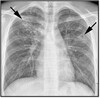

What pathology is shown here? How do we know?

A

Cystic fibrosis

-Haziness inside the airway is the mucus, bronchiectasis (dilation of the airways)